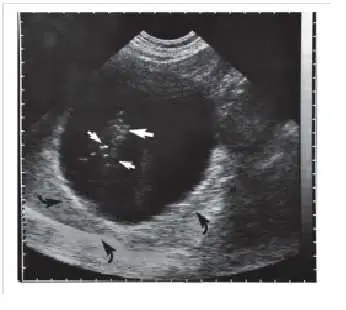

某病患的腎臟超音波影像如下圖,請問箭頭處的假影為何?

本題考核超音波假影(ultrasound artifact)的識別,特別是 B-mode 超音波中的距離模糊假影(range ambiguity artifact)。圖中腎臟超音波影像顯示腎臟下方出現一組與腎臟結構相似的假影,此為高脈衝重複頻率(pulse repetition frequency, PRF)導致回波時序錯亂所產生的典型表現。

影像為腎臟 B-mode 超音波橫斷面(transverse)影像,可見:

- 腎臟本體:位於影像中央,呈橢圓形,腎竇(renal sinus)回音較強(高回音),腎實質(renal parenchyma)回音較低,腎臟輪廓清晰。

- 白色箭頭(白箭,↑):指向腎竇區域內的強回音結構,為正常腎竇脂肪或血管結構。

- 黑色彎箭(黑箭,↵):位於腎臟下方(深部),指向一排與腎臟輪廓相似的低回音區域,此區域在解剖上不應存在明顯結構。這些黑箭所指的即為距離模糊假影:超音波機誤將來自腎臟本體的回波訊號,對應到下一個脈衝週期所計算的較淺深度,使腎臟的影像「複製」出現在腎臟下方的位置。

影像特徵符合 range ambiguity artifact 的典型外觀:假影位置在真實器官的深部,形狀與真實結構相近,但輪廓較模糊。